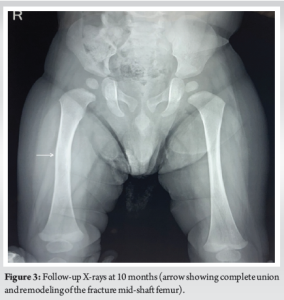

The next day, the baby was handed over to the mother and was kept on breastfeeding. After 5 days post-operative, both the mother and neonate were discharged and reviewed in the orthopedic outpatient department after 1 week, when the posterior splint was replaced with a toe-groin cast for another 2 weeks. On follow-up on the 25th day, a repeat X-ray showed abundant callus between fracture ends, and the cast was removed (Fig. 2). Clinical examination revealed no local tenderness and deformity with active, painless movements of both limbs, thus completing the treatment. At follow-up after 10 months, repeat X-ray shows complete healing of the fracture with no deformity and visible limb length discrepancy of the limb (Fig. 3).